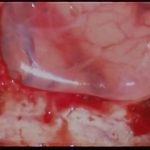

側頭葉膠芽腫

No.’16_129 摘出 前

No.’16_129 摘出 後